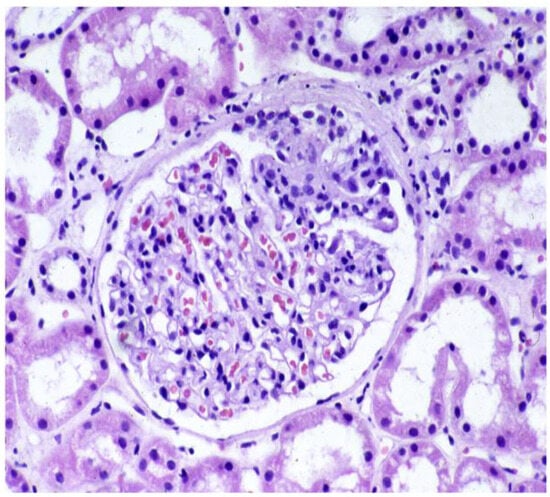

3.2. Recurrence of AAV and ANCA-GN After Kidney Transplantation and Outcomes and Therapy

- Nachman, P.H.; Segelmark, M.; Westman, K.; Hogan, S.L.; Satterly, K.K.; Jennette, J.C.; Falk, R. Recurrent ANCA-Associated Small Vessel Vasculitis after Transplantation: A Pooled Analysis. Kidney Int. 1999, 56, 1544–1550. [Google Scholar] [CrossRef]

- Gera, M.; Griffin, M.-D.; Specks, U.; Leung, N.; Stegall, M.-D.; Fervenza, F.-C. Recurrence of ANCA-Associated Vasculitis Following Renal Transplantation in the Modern Era of Immunosupression. Kidney Int. 2007, 71, 1296–1301. [Google Scholar] [CrossRef]

- LAU, D.; SUMMERS, S.; AMOS, L.; SIMPSON, I.; MULLEY, W. Recurrence of Anti-neutrophil Cytoplasmic Antibody Vasculitis in the Kidney Allograft. Nephrology 2012, 17, 16–19. [Google Scholar] [CrossRef]

- Berden, A.E.; Ferrario, F.; Hagen, E.C.; Jayne, D.R.; Jennette, J.C.; Joh, K.; Neumann, I.; Noël, L.-H.; Pusey, C.D.; Waldherr, R.; et al. Histopathologic Classification of ANCA-Associated Glomerulonephritis. J. Am. Soc. Nephrol. 2010, 21, 1628–1636. [Google Scholar] [CrossRef]

- Göçeroğlu, A.; Rahmattulla, C.; Berden, A.E.; Reinders, M.E.J.; Wolterbeek, R.; Steenbergen, E.J.; Hilbrands, L.B.; Noorlander, I.; Berger, S.P.; Peutz-Kootstra, C.J.; et al. The Dutch Transplantation in Vasculitis (DUTRAVAS) Study. Transplantation 2016, 100, 916–924. [Google Scholar] [CrossRef]